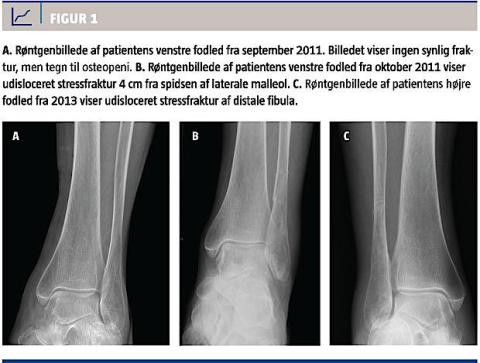

En 81-årig kvinde blev tilset på en akutafdeling i september 2011 pga. smerter på ydersiden af venstre fodled. Smerterne havde stået på i halvanden uge og var opstået uden kendt traume. Hun var særdeles aktiv og gik flere kilometer dagligt. Hun var i øvrigt sund og rask bortset fra osteoporose, som hun havde været i behandling for siden 2005. Hun tog tablet alendronat 70 mg ugentligt. Der blev taget et røntgenbillede (Figur 1A), som ikke viste nogen synlig fraktur, men følgende tegn på ostopeni: øget røntgengennemskinnelighed af knoglen og tyndt knoglecortex [2].

I oktober 2011 sendte hendes egen læge hende til røntgenundersøgelse af venstre fodled igen pga. fortsatte smerter. Røntgenbilledet af fodleddet viste udisloceret stressfraktur 4 cm fra spidsen af den laterale malleol (Figur 1B). Patienten blev behandlet konservativt med Aircast og fuld støtte i seks uger. Ved efterfølgende kontroller i ortopædkirurgisk ambulatorium var der klinisk og radiologisk fremgang, og hun blev afbandageret.

I 2013 blev hun på ny henvist til et ortopædkirurgisk ambulatorium nu med smerter på ydersiden af højre fodled uden kendt traume. Et røntgenbillede af fodleddet viste udisloceret distal fibula stressfraktur (Figur 1C). Hun blev behandlet med Aircast, og behandlingen kunne afsluttes med patienten i velbefindende efter seks uger.